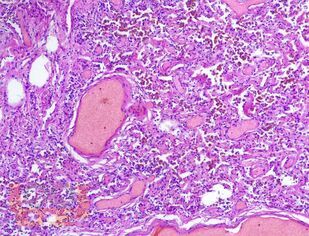

Учебное пособие разработано по дисциплине «Патологическая анатомия - патологическая анатомия головы и шеи» в соответствии с Федеральным государственным образовательным стандартом высшего профессионального образования для студентов, обучающихся по основным образовательным программам высшего образования - программам специалитета по специальности «Стоматология».

В учебном пособии представлен теоретический материал, перечень макропрепаратов и микропрепаратов, демонстрирующих типовые проявления патологических процессов. В цветных иллюстрациях и в описании микропрепаратов сделан акцент на наиболее важных гистологических изменениях, позволяющих на светооптическом уровне диагностировать и дифференцировать состояния, отклоняющиеся от нормы, в том числе с использованием различных гистологических окрасок. Пособие помогает выделить главные аспекты изучаемых патологических процессов, организовать и конкретизировать учебный процесс.